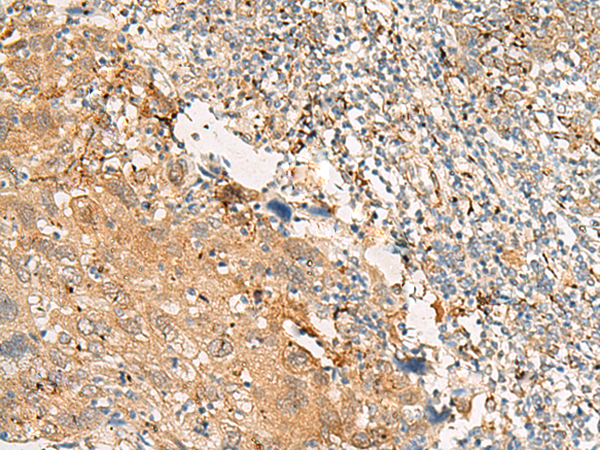

分类: 科研抗体货号: P06575别名: GPIV; GPVI; BDPLT11应用: WB,IHC反应种属: Human